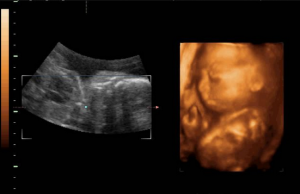

“4D”是“四維”的縮寫。第四維是指時間這個矢量,所以也被稱作實時三維。對於超聲學來說,4D超聲技術是彩超行業的革命性突破,最先由韓國麥迪遜公司率先研發出並開始推廣。4D超聲技術就是採用3D超聲圖像加上時間維度參數,該革命性的技術能夠實時獲取三維圖像,超越了傳統超聲的限制。它提供了包括腹部、血管、小器官、產科、婦科、泌尿科、新生兒和兒科等多領域的多方面的套用。

四維彩超同其它超聲診斷過程相比,可以實時的觀察人體內部器官的動態運動。臨床醫生和超聲科大夫可以檢測和發現各種異常,從血管畸形到遺傳性綜合徵。四維彩超能夠多方位、多角度地觀察宮內胎兒的生長發育情況,且可以為早期診斷胎兒先天性體表畸形和先天性心臟疾病提供準確的科學依據。過去的B超設備只能檢查胎兒的生理指標,而四維彩超還能對胎兒的體表進行檢查,如唇裂,脊柱裂,大腦、腎、心臟、骨骼發育不良等,以便儘早的進行治療。生個聰明健康的小寶寶,並且將寶寶的樣子和動作製作成照片或VCD,讓寶寶擁有最完整的0歲相冊,這已經不再是幻想。

臨床廣泛套用的B超或彩超雖然能夠判斷胎兒發育是否正常,但只有專業醫生看得懂,四維彩色超聲診斷儀能能夠自動為胎兒進行宮內拍“寫真”和進行動態錄像,為眾多的準媽媽們增添無數安心和情趣。四位彩超使用的儀器叫‘四維(4D)彩色超聲診斷儀’,這種技術能夠實時獲取三維圖像,提供包括腹部、血管、小器官、產科、婦科、泌尿科、新生兒和兒科等多領域的多方面的套用。

三維彩超、四維彩超的圖像則是後期生成的,並不是說觀察到的圖像就是三維、四維的,而是仍然用普通彩超觀察,然後通過儀器中的轉換軟體將觀察到的平面圖像轉成三維、四維的立體圖像,說得更直白一點,如果將你的家用電腦中裝上類似軟體,你就可以把普通B超的圖像自己在家裡轉換成立體的了。在診斷的意義上,三維彩超、四維彩超沒有任何對診斷更有利的地方,只不過是不懂得B超圖像的人也能看出模樣而已。它們的意義也就在於,您能看見寶寶還在肚子裡的模樣了。

三維彩超和四維彩超的區別就在於在一個“時間維”,也就是說,三維彩超是圖片,四維彩超是錄像,可以讓孕媽媽看到胎兒一連串的動作。

四維彩超是動態的,三維彩超是靜態的,所以四維看起來會更清楚明晰,三維彩超只能是某個時間點上的照片,四維彩超的就可以做成DV那樣連續的,可以刻錄光碟。三維彩超和高清四維彩超一樣的有排畸的作用,高清四維彩超更加精確。

四維彩超不再是僅僅感覺寶寶的呼吸和運動,而是可以親眼目睹他們的一舉一動和乖巧的秀容。更為重要的是,四維彩超能夠多方位、多角度地觀察宮內胎兒的生長發育情況,為早期診斷胎兒先天性體表畸形和先天性心臟疾病提供準確的科學依據。